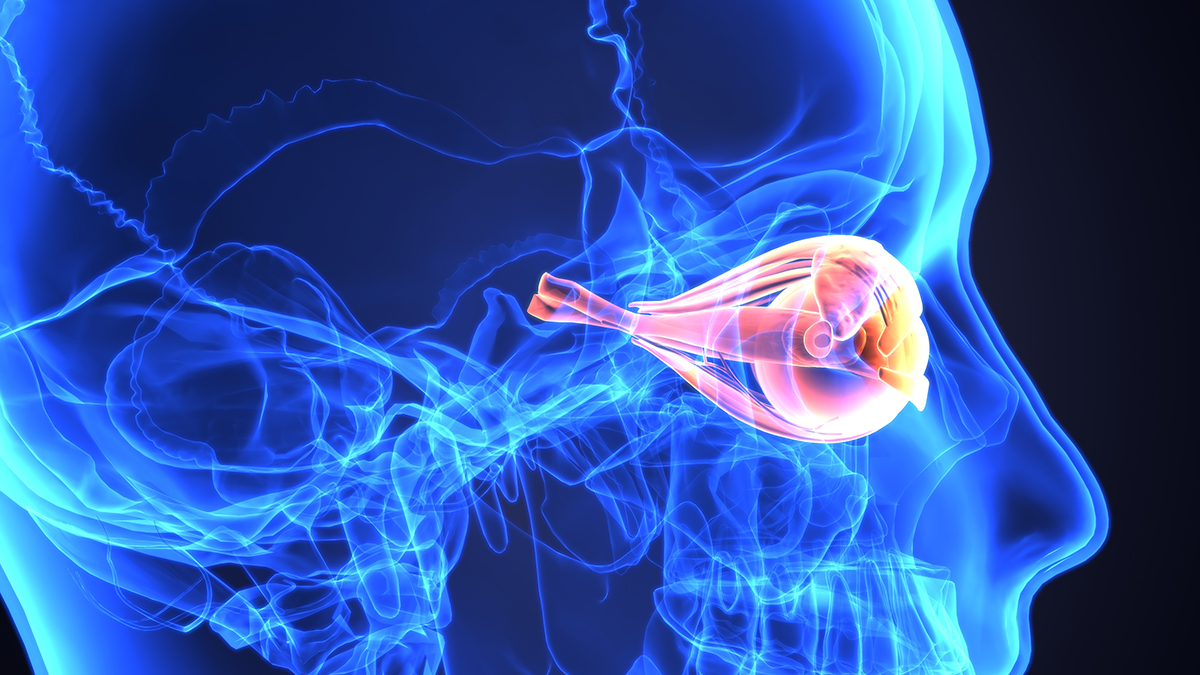

進行した緑内障疾患における視神経 / Optic nerve in advanced glaucoma disease.

視力は回復しないという緑内障への思い込み

緑内障は日本人の失明原因の第1位で、40歳以上の20人に1人が発症する。

西洋医学では、眼科医は「緑内障は治らず、徐々に悪化して、失明することもある」、「視神経は脳神経の一つで、一度害されると回復しない。失われた視野や視力は二度と回復しない」と言うが、それは何の証拠もない思い込みである。

中国伝統医学で診断し、診断結果に基づいて視神経の治療をすると、緑内障の視野は改善する。

日本人に多い正常眼圧緑内障(眼圧21以下)の原因の多くは胃腸虚弱 (消化吸収力が弱い)が原因である。

また、心理的トラウマ、精神的ストレス、自律神経失調、血流障害、エネルギー代謝の低下、食生活の不摂生、多量の飲酒、ひどい近視、低体温、冷え性、低血圧、眼科手術なども原因となる。

また、更年期の内分泌器官の機能低下(エストロゲン低下) とそれに伴う交感神経系の機能亢進なども緑内障を悪化させる。

西洋医学では、「約100万本の神経線維の束から徐々に線維が減っていくため、最悪の場合、視野のうち、減った線維が担当していた部分が見えなくなり、失明する」と言うが、障害を受けた視神経が完全に死滅するまでに数年かかると言われており、ある時点では障害の程度が異なる視神経が混在している。

3d illustration of human body eye anatomy

瀕死の状態の視神経はまだ完全には死んでおらず、蘇生させられる。

また、視野検査の視野50%欠損イコール視神経50%死減というわけではない。

たとえば50%のうち20%の視神経は障害を受けて機能低下しているが死滅してはいない場合、治療により視野欠損の進行は止まり、この20%の視神経は機能が回復し、視野欠損は改善する。

この20%を放置しておけば2〜3年で本当に死滅、治療を続ければ3〜4年は視野が改 善し続けるようだ。